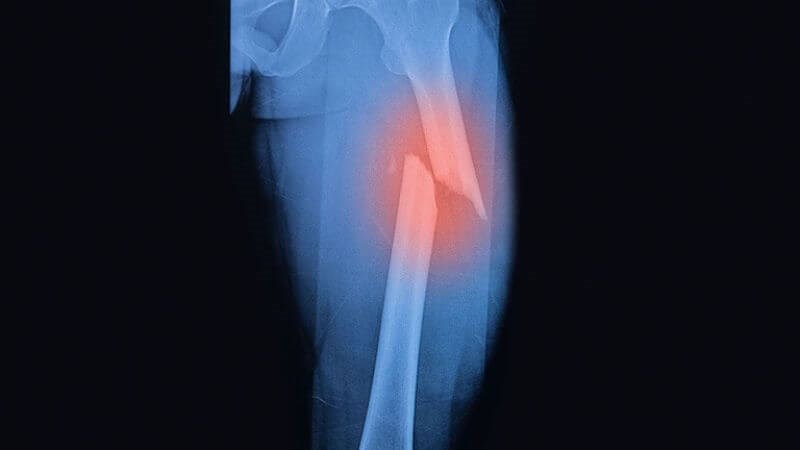

- Gãy thân xương đùi: là vết thương ở giữa xương đùi. Đây là loại gãy nặng nề cần được xử trí rất khẩn cấp.

Để đánh giá rõ vị trí cũng như loại chấn thương, bác sĩ sẽ chỉ định chụp X-quang hoặc chụp cắt lớp vi tính để đánh giá tình trạng gãy xương đùi. Một số loại gãy xương đùi bao gồm:

- Gãy ngang: vết gãy chạy ngang qua xương đùi theo một đường thẳng.

- Gãy chéo vát: vết gãy tạo thành một góc < 90 độ so với xương đùi.

- Gãy phức tạp: có nhiều mảnh nhỏ của xương đùi.

- Gãy xương hở hay gãy kín: gãy hở là xương đâm ra bên ngoài da.

Chụp X-quang giúp chẩn đoán gãy xương đùi